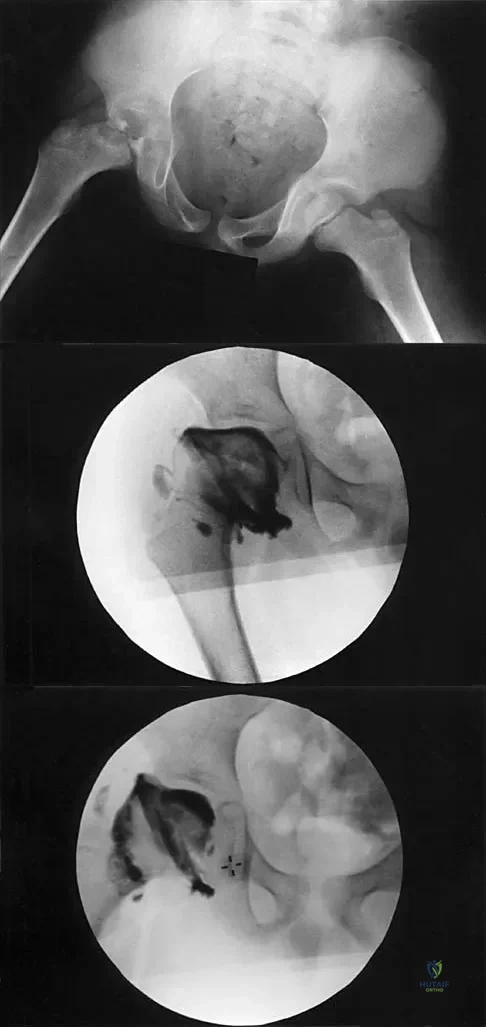

Question 54High Yield

A 7-year-old patient has had a painless limp for several months. Examination reveals pain and spasm with internal rotation, and abduction is limited to 10 degrees on the involved side. Management consists of 1 week of bed rest and traction, followed by an arthrogram. A maximum abduction/internal rotation view is shown in Figure 40a, and abduction and adduction views are shown in Figures 40b and 40c. The studies are most consistent with

Explanation